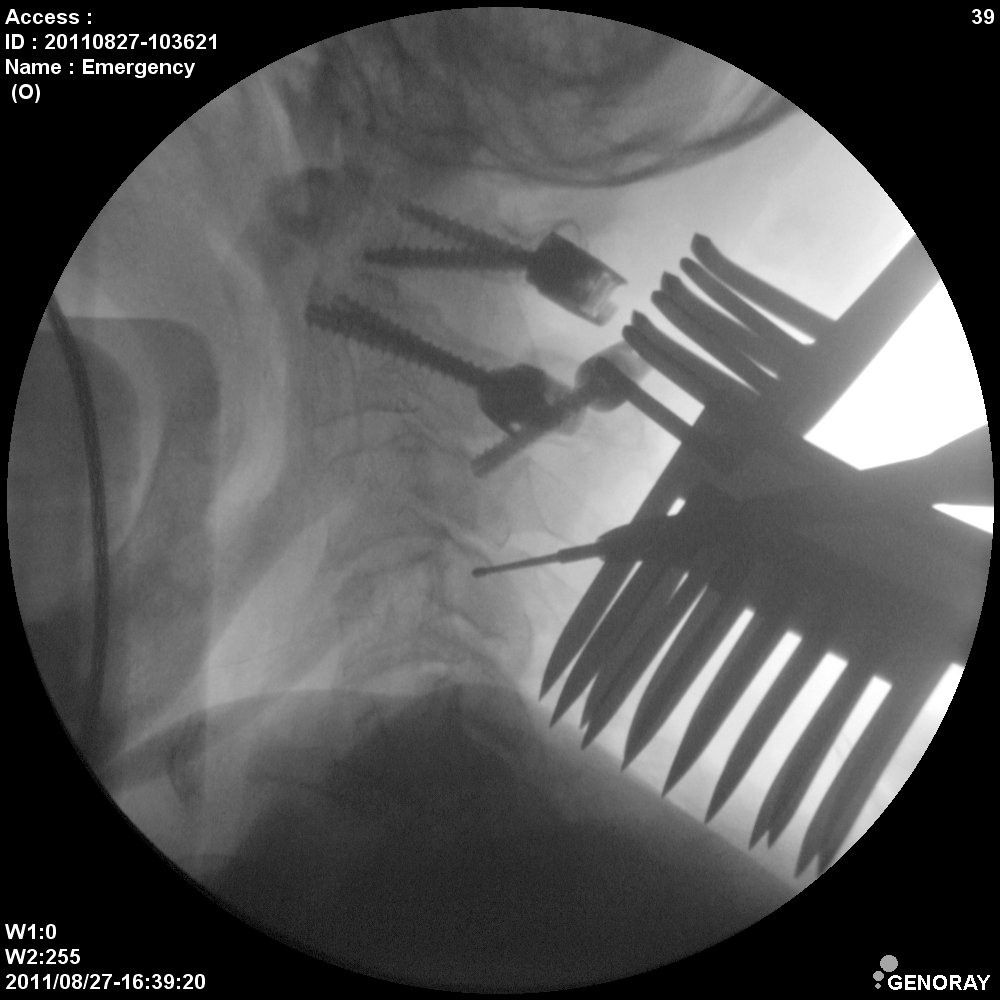

Аппарат применяется в различных областях медицины, таких как хирургия, ортопедия, педиатрия, травматология, урология и многих других. «АРХМ-РЕНЕКС» имеет широкий диапазон перемещений, легко позиционируется во всех направлениях, а так же имеет не большие габариты и вес обеспечивающие маневренность и простоту перемещений.

В качестве приемника используется усилитель рентгеновского изображения (УРИ) с ПЗС-матрицей 1024х1024 пикселей. Мощность рентгеновского питающего устройства 2,2 кВт.

- Непрерывная и импульсная рентгеноскопия с цифровой обработкой изображения.

- Режим низкодозовой рентгеноскопии.

- Цифровая рентгенография.